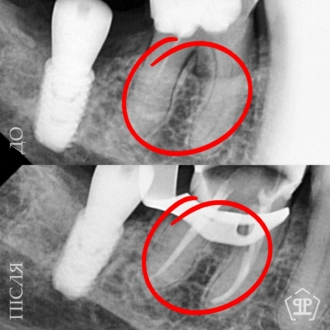

Во время диагностики обнаружен отлом фрагмента инструмента в корневом канале. Выполнено его безопасное извлечение, повторное перелечивание каналов, очистку и герметичное пломбирование.